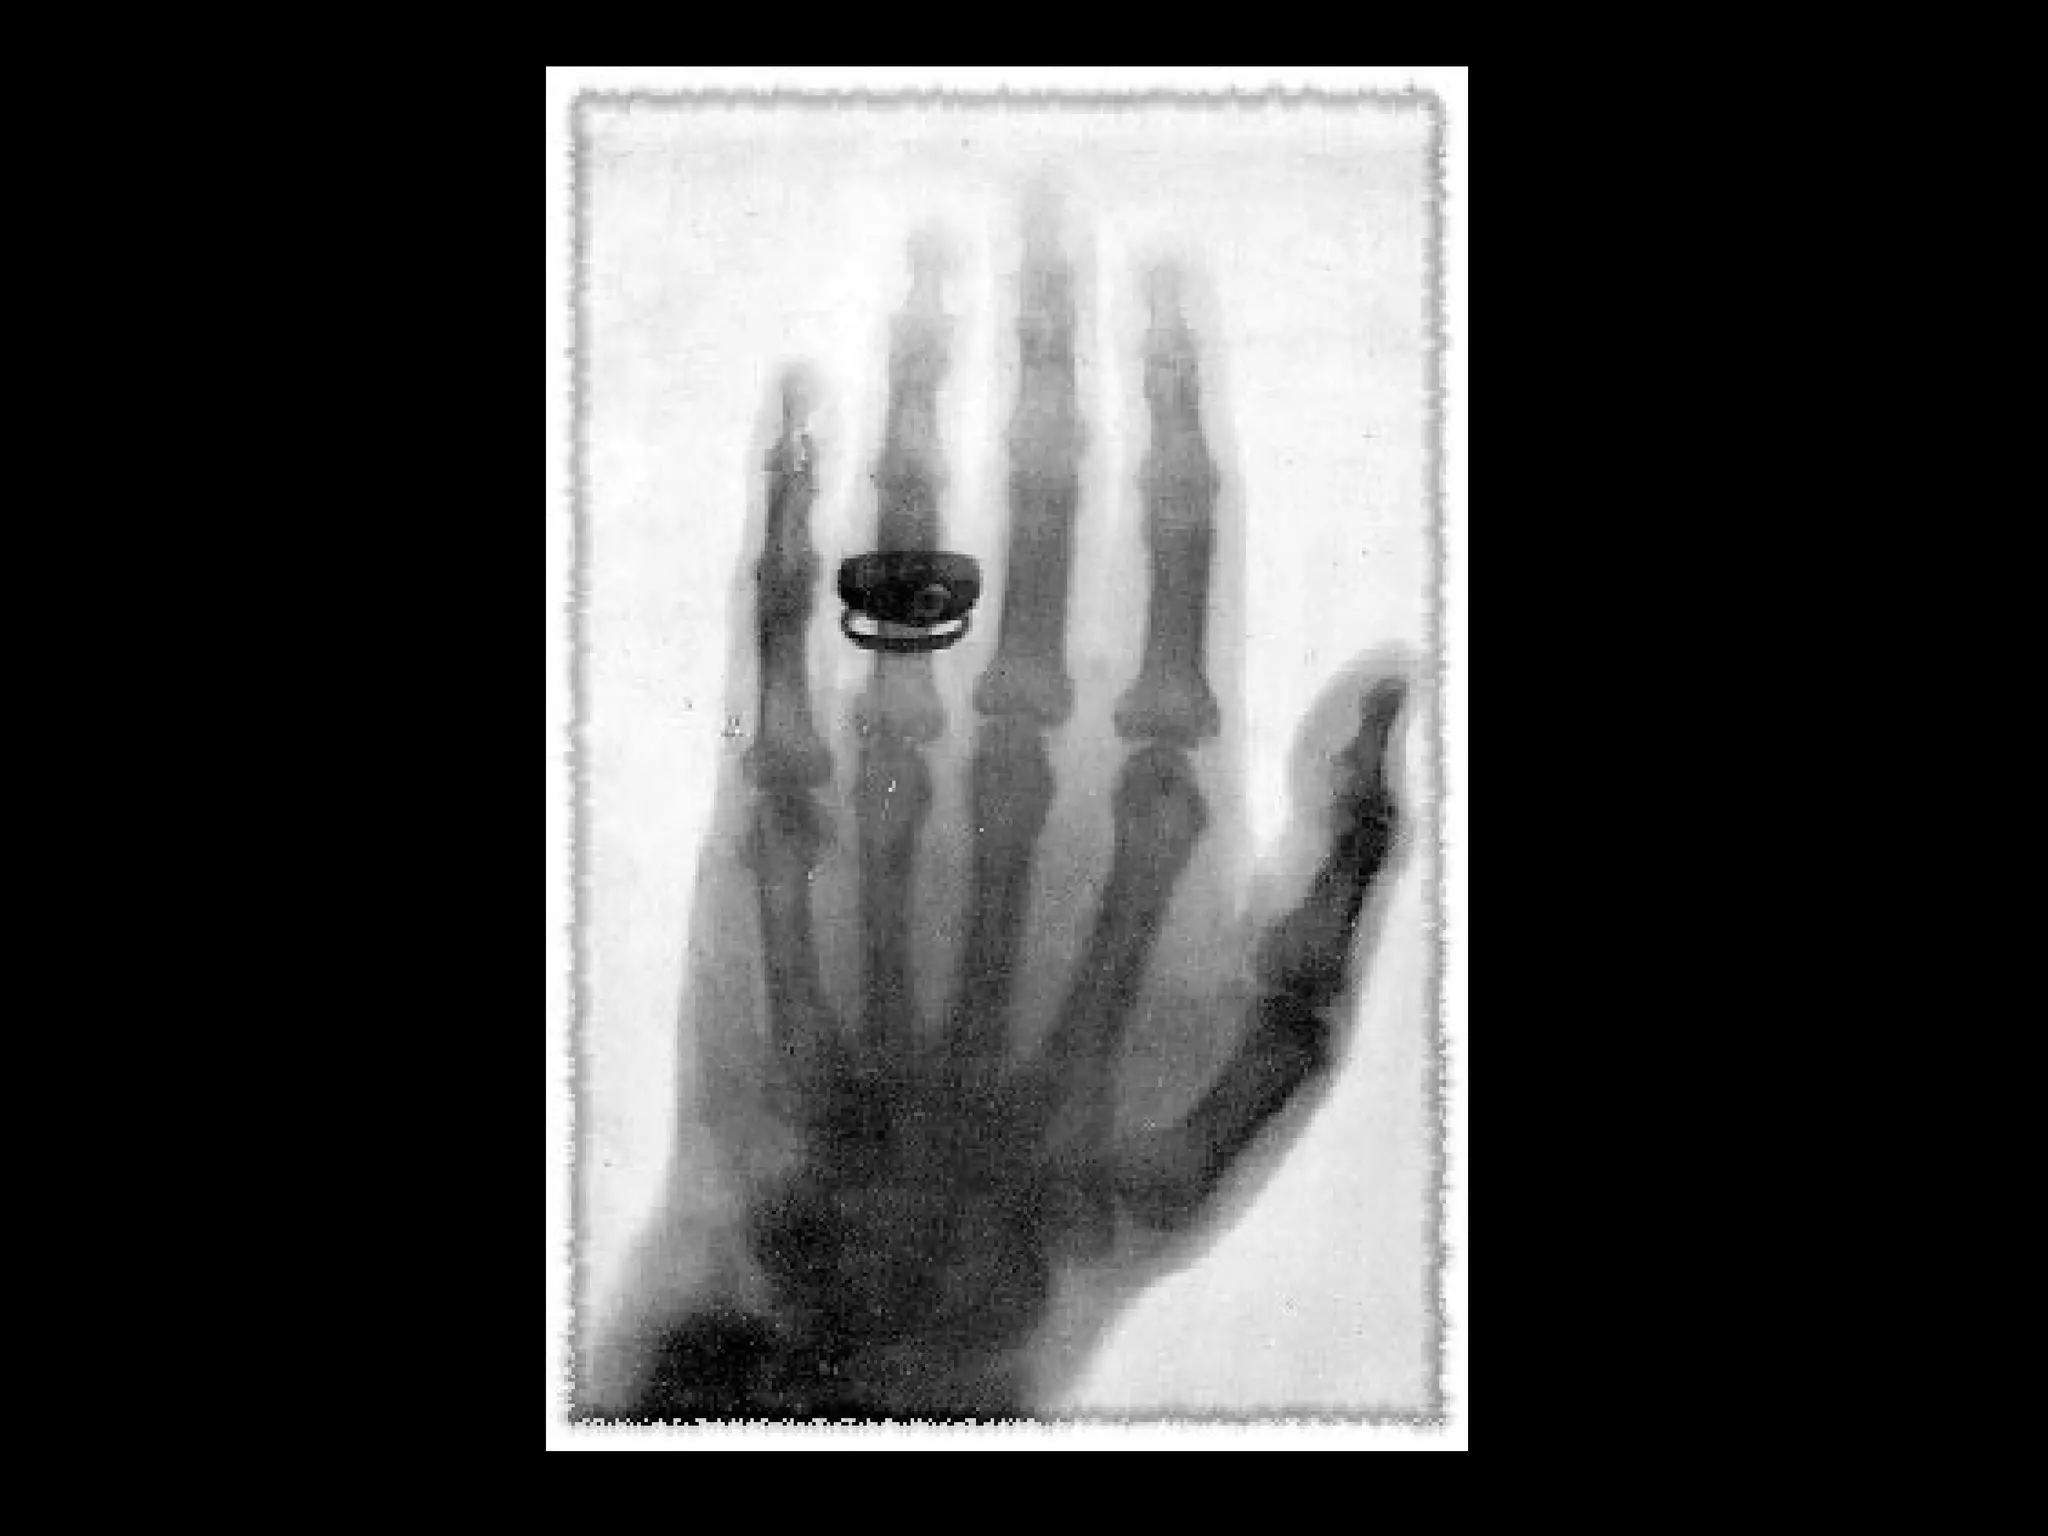

First X ray made in public.

• Hand of the famed

anatomist, Albert von

Kölliker, made during

Roentgen's initial

lecture before the

Würzburg Physical

Medical Society on

January 23, 1896.

• 63.

First X raymade in public. • Hand of the famed anatomist, Albert von Kölliker, made during Roentgen's initial lecture before the Würzburg Physical Medical Society on January 23, 1896.